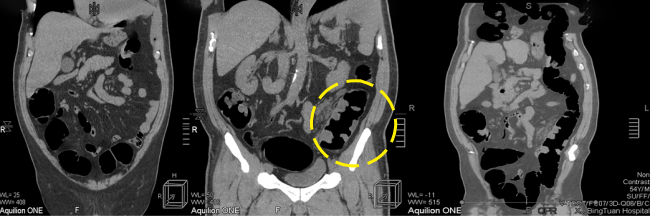

病例二 女,63歲,以持續(xù)性腹部疼痛不適半天就診。既往有冠心病15年、心房纖顫史5年余;高血壓5年。

采用心臟+主動(dòng)脈血管一站式檢查,可見(jiàn)該患者腸系膜上動(dòng)脈及其分支充盈缺損,同時(shí)顯示左心耳內(nèi)多發(fā)血栓, 隨時(shí)有血栓脫落的危險(xiǎn)。

全麻下行剖腹探查、 腸系膜上動(dòng)脈血栓取出術(shù), 病理顯示血栓樣組織機(jī)化。

患者術(shù)后第三天,由于右側(cè)肢體活動(dòng)障礙,語(yǔ)言受限,急查CT發(fā)現(xiàn)多發(fā)腔隙性腦梗塞,MRI檢查后明確左側(cè)急性梗死。

腸系膜上動(dòng)脈栓塞栓子多來(lái)源于心臟,也可來(lái)自于主動(dòng)脈壁粥樣硬化斑塊脫落。腸系膜上動(dòng)脈從腹主動(dòng)脈分出,主干口徑又較大,脫落的栓子易于進(jìn)入,在血管狹窄或分叉處導(dǎo)致血管栓塞。

臨床表現(xiàn)主要有“Bergan三聯(lián)征”1 、劇烈而沒(méi)有相應(yīng)體征的腹痛。2器質(zhì)性心臟病和并發(fā)心房纖顫的心臟病。3、胃腸排空障礙表現(xiàn)如腹瀉、 血便。

640層寬體探測(cè)器CT掃描速度快,可進(jìn)行大范圍心血管一站式檢查,快速排除血管病變,且由于探測(cè)機(jī)單元只有0.5mm,對(duì)于一些微小的病變也能清晰顯示。